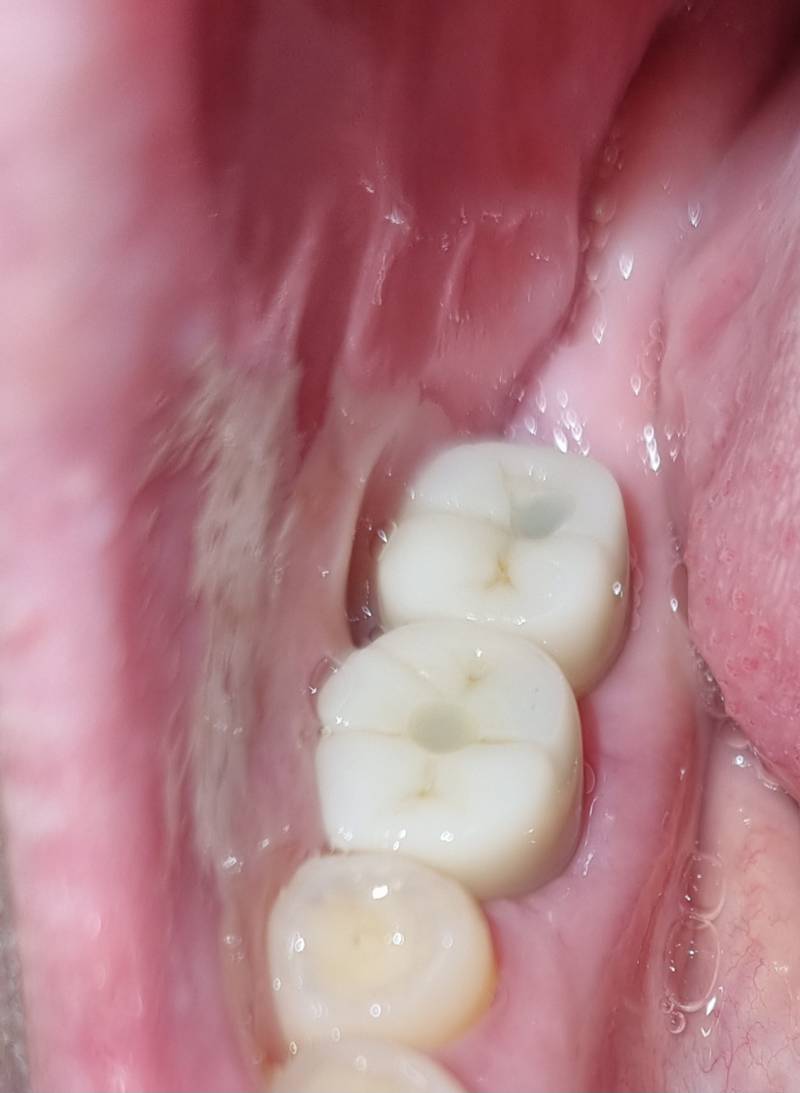

임플란트가 원래 이렇게 티나..? ㅎㅇㅈㅇ

전문가는아닌데 대부분의 보철물이 티나긴함

컬러차트로 다른치아와 비슷한 색으로 뽑아도 티남..... 그리고 치아볼살 뜯거나 쎄게 물고있어?? 아니면 교합안맞나

뭔가 씹고나서 낑기는듯한 느낌나서 불편해..

그리고 색깔보다 치아가 굴곡이없이 그냥 선만그어놓은 느낌이야..

님 볼살이지금글케보이자나.... 생기는이유는 넘 다양함 임플란트하면 원래 음식물 엄청껴 딴데도 가바

치아가 굴곡이 없어 보이기는 하네

근데 저 나사 들어가는 공간은 어쩔 수 없어

둘다 너무 굴곡 없는 치아 모양이기는 하다

그치..이럴수도있어? 굴곡이 너무없어

아니 보통 교합 때문에 저렇게 안만들지

만질때 매끈할 것 같음. 다른 치과 갈 수 있어?

웅 저구멍은 어쩔수없는거 아는데 너무 굴곡없이 선만그어놓은 느낌이라..